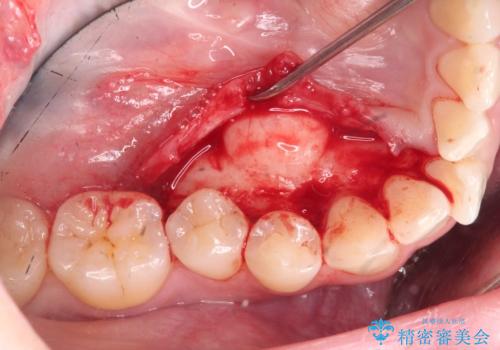

矯正の後戻りを防ぐ骨隆起の切除

- 矯正治療に先立ち、舌の収まりを改善し矯正治療後の後戻りリスクを下げるため、大きな下顎隆起の切除を計画します。

このあと、両側の隆起を除去し、舌の収まりが楽になったと喜んでいただくことができました。